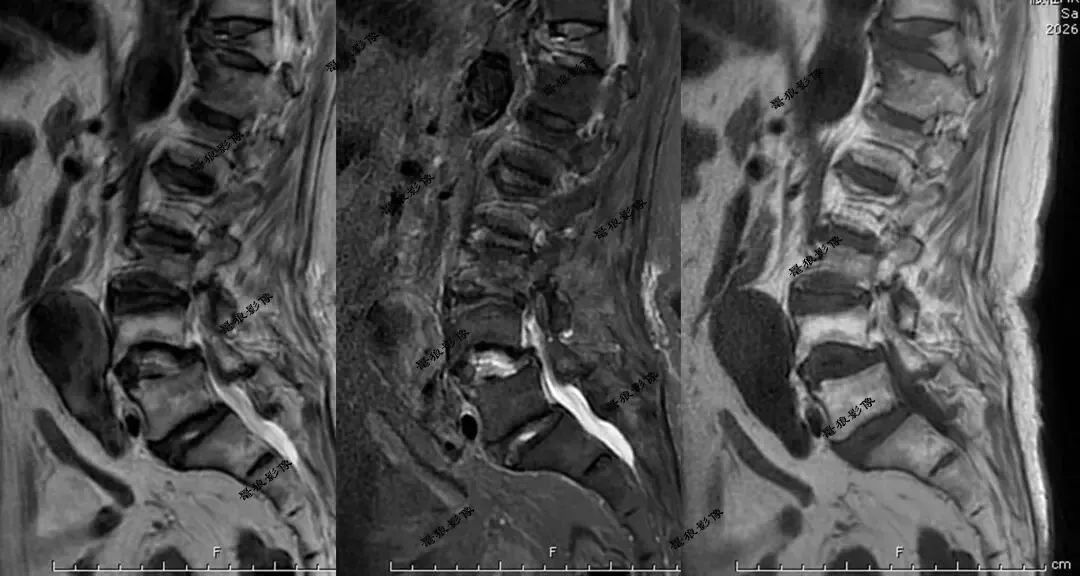

二、腰椎MR(术前)

考虑腹主动脉下段动脉瘤并附壁血栓。